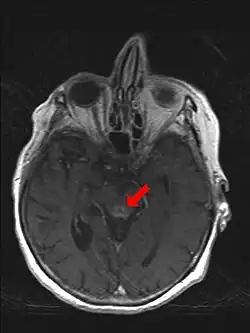

Kontrastmittel-Anreicherung periaquäduktal bei Wernicke-Enzephalopathie im MRT

Zu Grunde liegt ein Vitamin-B1-Mangel (Thiamin), der zu Störungen im Kohlenhydratstoffwechsel durch Versagen einer energiereichen Phosphorylierung führt. Nach einer ödematösen Schwellung des Gehirns kommt es später auch zur Einblutung und Kapillarsprossung an bestimmten Stellen des Gehirns (Corpora mamillaria, hypothalamische Kerngebiete um den III. Ventrikel, Lamina tecti und periaquäduktales Grau mit Okulomotoriuskerngebieten). Es folgt eine Atrophie dieser Strukturen.